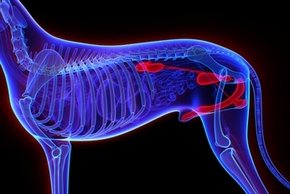

Nos conseils pour traiter l'arthrose chez le chien

Saviez-vous que l'arthrose ne touche pas que les humains ? Les chiens aussi peuvent en être victimes. Et autant dire que l'arthrose du chien âgé n'est pas une mince affaire. Douloureuse et impossible à soigner, cette pathologie canine peut être une vraie plaie pour nos compagnons. Heureusement, il existe de bons moyens d’apaiser ses symptômes. Dans cet article, apprenez à soulager l'arthrose du chien !